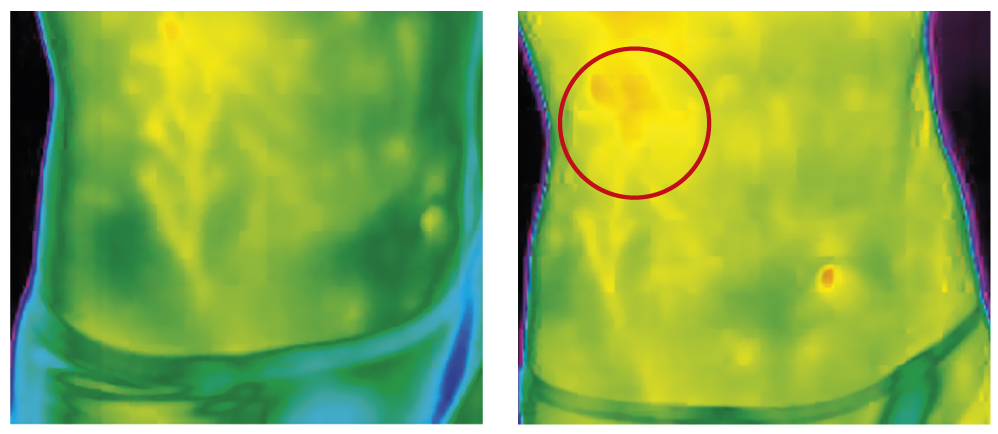

Оценка функционального состояния ЖКТ осуществлялась с помощью метода тепловидения. Исследование кала выполнено согласно Отраслевому стандарту 91500.11.0004-2003 «Протокол ведения больных. Дисбактериоз кишечника» (приказ Минздрава России от 09.06.2003 г. № 231).

С помощью прибора тепловизора было определено состояние органов пищеварения в исходном состоянии (до начала приёма препаратов) и после окончания лечения. В группе водного поло нарушения функций ЖКТ (повышение интенсивности излучения в области печени, кишечника, желудка), идентифицированные с помощью тепловидения, наблюдались у 29%, в группе биатлона — у 53%, в группе баскетбола — у 14% (рис. 1).

Рис. 1. Пример термограммы спортсменки с повышенной интенсивностью излучения в проекции печени.